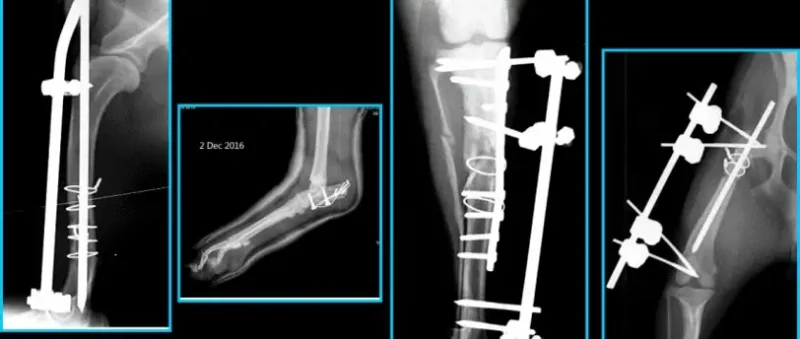

- Bước 1: Tiến hành thăm khám và kiểm tra tổng quát cho thú cưng bao gồm nhịp tim, hô hấp , phản xạ thần kinh. Ngoài ra, chúng tôi sẽ tiến hành chụp X-quang hoặc CT chuyên sâu để xác định được mức độ nghiêm trọng tổn thương trong xương, nhằm chẩn đoán được tình trạng bệnh của thú cưng.

- Bước 2: Sau chẩn đoán, phòng khám sẽ báo kết quả cho chủ nuôi để có thể quyết định thực hiện theo phác đồ điều trị phù hợp, bao gồm các quá trình thực hiện ca phẫu thuật và tỷ lệ thành công là bao nhiêu phần trăm. Việc cố định xương bằng nẹp vít, ghép xương hay đóng đinh nội tủy, chỉnh hình xương khớp cần phải xác định rủi ro có thể xảy ra nhằm đưa phác đồ phẫu thuật phù hợp nhất và bắt đầu tiến hành.